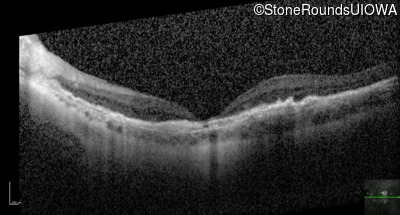

Optical Coherence Tomography - Right - 20/200 +2

Exemplar / OCT Stack